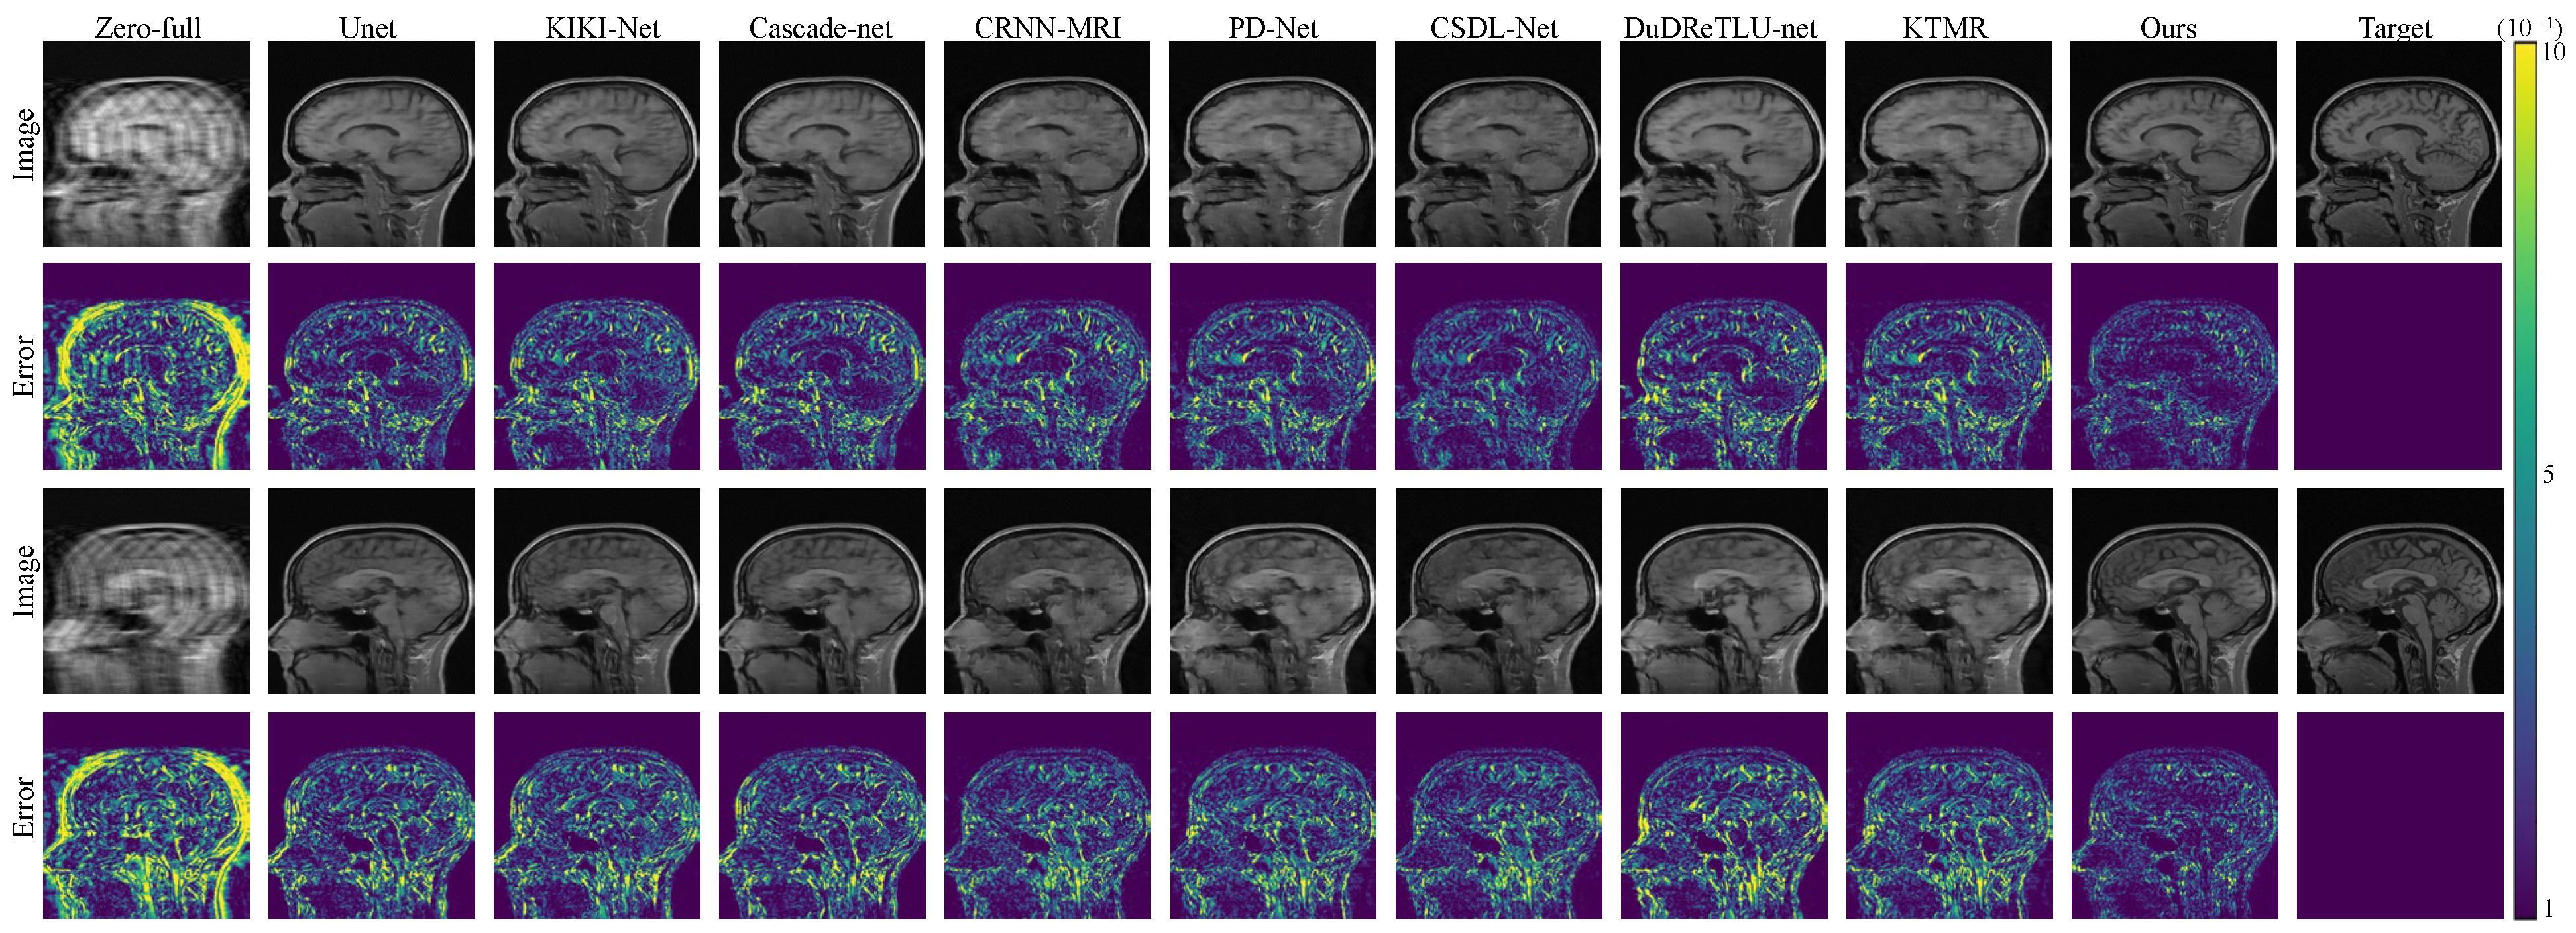

To visually illustrate the effectiveness of our approach, we present comparison results for 4× and 8× acceleration rates in Figure 2 and Figure 3. These figures clearly demonstrate that our framework excels in preserving intricate structures, creating more natural and intricate texture features, and producing clearer and more realistic reconstructed images compared to other methods. Furthermore, our method excels in achieving high-fidelity reconstructions even when dealing with highly under-sampled measurements. Figure 2 and Figure 3 also display error maps corresponding to various comparative methods, highlighting that our approach yields fewer errors at different under-sampling rates.

Figure 3. The reconstruction results and error maps are compared among 8 algorithms under 8× acceleration on the FastMRI dataset.

Electronics 12 04742 g003